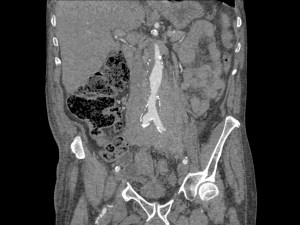

Paciente con aneurisma de aorta con dolor abdominal difuso y bilateral. Sin otros hallazgos clínicos y ni analíticos. Constantes vitales estables.

El TC abdominal en fase portal y excretora evidencian una masa que compromete ambos uréteres, más acentuada a la izquierda, produce hidronefrosis bilateral, hallazgo muy infrecuente en el linfoma. Además es isodenso con respecto al músculo, rodea la aorta por la parte anterior, no la desplaza hacia adelante y está en situación infrarrenal predominantemente. No hay adenopatías. Solución: estamos ante una Fibrosis Retroperitoneal.